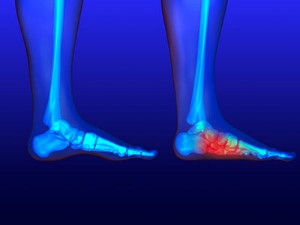

Causes and Treatment for Heel Pain

Heel pain, a common ailment, can be a source of discomfort that interferes with daily activities. The causes of heel pain can vary, with one of the most prevalent being plantar fasciitis. This condition involves inflammation of the plantar fascia, the thick band of tissue that supports the arch of the foot. Other common culprits include Achilles tendonitis, heel spurs, and bursitis. The good news is that heel pain is often treatable. Treatment options for heel pain range from conservative methods to more advanced interventions. Resting and performing gentle stretching exercises can provide relief, while custom-made orthotics may help distribute pressure more evenly. In severe or persistent cases, minimally invasive procedures such as corticosteroid injections may be recommended. Consulting a podiatrist is crucial in determining the underlying cause, in addition to guiding you toward the most suitable treatment plan. By addressing the root cause and following a tailored treatment regimen, you can take significant steps towards a pain-free and active lifestyle. It is strongly suggested that you visit a podiatrist who can accurately diagnose the cause for your heel pain and treat it accordingly.

Causes of Heel Pain

Heel pain is often associated with plantar fasciitis. The plantar fascia is a band of tissues that extends along the bottom of the foot. A rip or tear in this ligament can cause inflammation of the tissue.

Achilles tendonitis is another cause of heel pain. Inflammation of the Achilles tendon will cause pain from fractures and muscle tearing. Lack of flexibility is also another symptom.

Heel spurs are another cause of pain. When the tissues of the plantar fascia undergo a great deal of stress, it can lead to ligament separation from the heel bone, causing heel spurs.

Heel Pain

Have you ever gotten up from a chair or out of bed in the morning, and upon taking that first step, feel like your heel has stepped on a tack? Many people experience a feeling of sharp pain which radiates into their arch from their heel and which does not allow them to put their heel on the floor. Sometimes they need to sit back down, stand only on their toes and use the wall for balance. If you can take a few steps, it seems to go away and lessen, allowing you to then resume your activity. Later, throughout your day and after a period of rest, it can happen again. If this sounds familiar you may be suffering from your first attack of heel pain.

Heel pain is a debilitating condition that affects day to day activities. Running and walking both causes stress on the heel because the heel is the part of the foot that hits the ground first. This means that the heel is taking on your entire weight. Diagnosis and treatments for heel pain can be easily found through your podiatrist.

Plantar Fasciitis

One of the main causes of heel pain is a condition known as plantar fasciitis. The plantar fascia is a band of tissue that extends along the bottom of the foot, from the toe to the bottom of the heel. A rip or tear in this ligament can cause inflammation of these tissues, resulting in heel pain. People who do not wear proper fitting shoes are often at risk of developing problems such as plantar fasciitis. Unnecessary stress from ill-fitting shoes, weight change, excessive running, and wearing non-supportive shoes on hard surfaces are all causes of plantar fasciitis.

Achilles Tendonitis

Achilles tendonitis is another cause of heel pain. Similar to plantar fasciitis, inflammation of the Achilles tendon will cause heel pain due to stress fractures and muscle tearing. A lack of flexibility of the ankle and heel is an indicator of Achilles tendonitis. If left untreated, this condition can lead to plantar fasciitis and cause even more pain on your heel.

Heel Spur

A third cause of heel pain is a heel spur. A heel spur occurs when the tissues of the plantar fascia undergo a great deal of stress, leading to a separation of the ligament from the heel bone entirely. This results in a pointed fragment of bone on the ball of the foot, known as a heel spur.